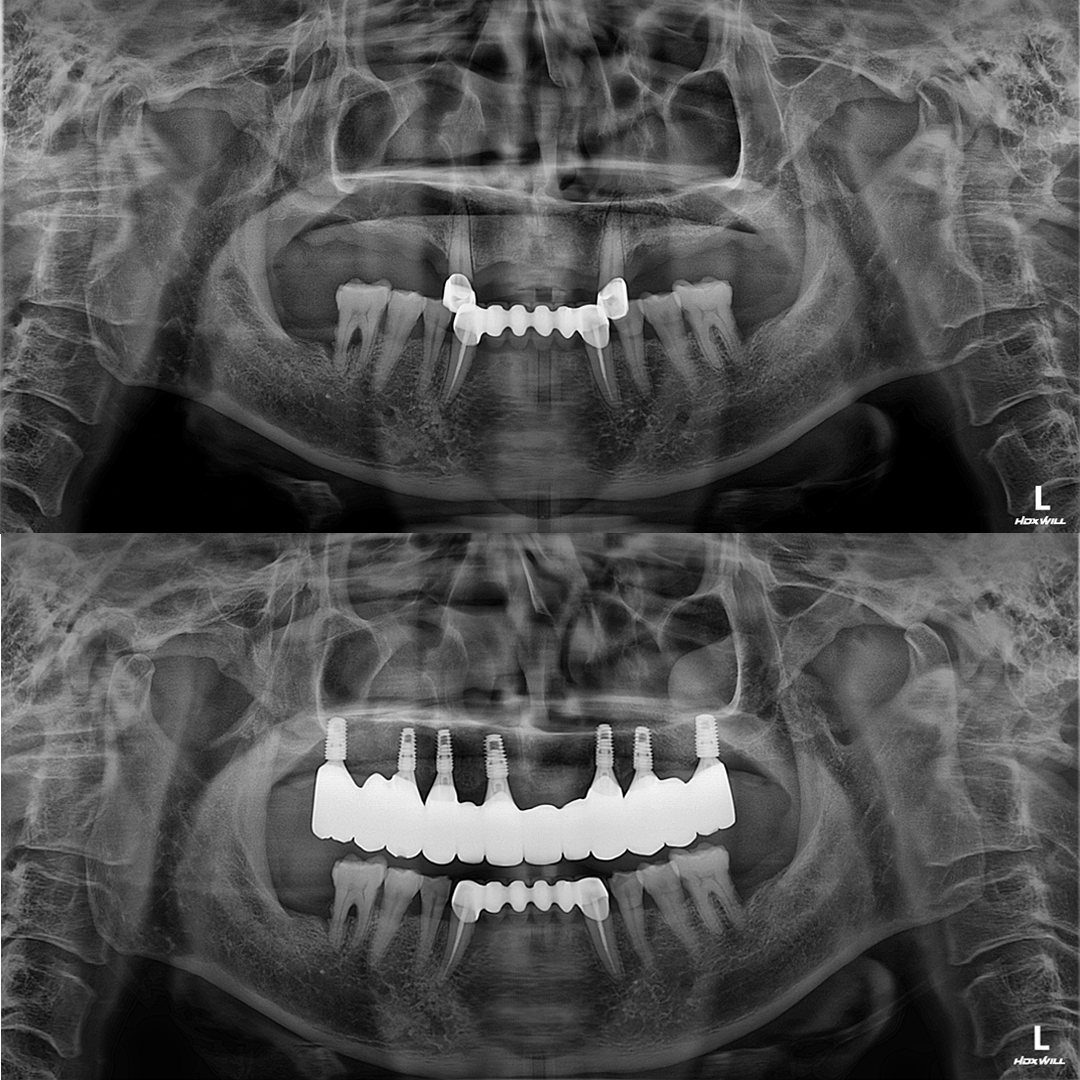

전체 임플란트

상·하악 전체 치아를 대체하는 임플란트로 최소한의 식립을 통해

자연치아와 비슷한 기능을 수행할 수 있도록 합니다.